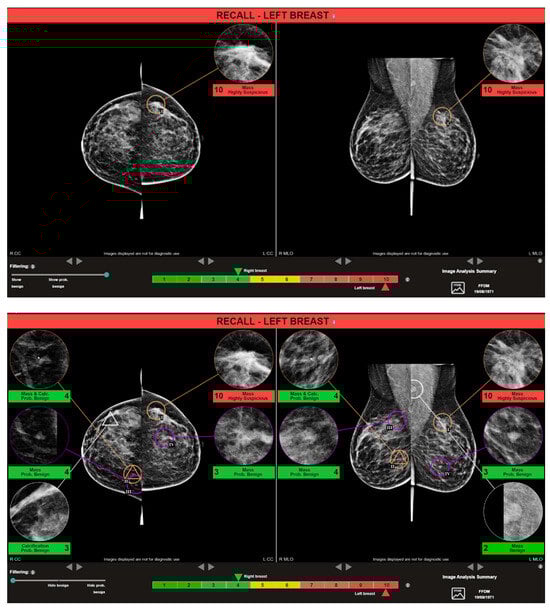

2.5. AI System for Mammogram Analysis